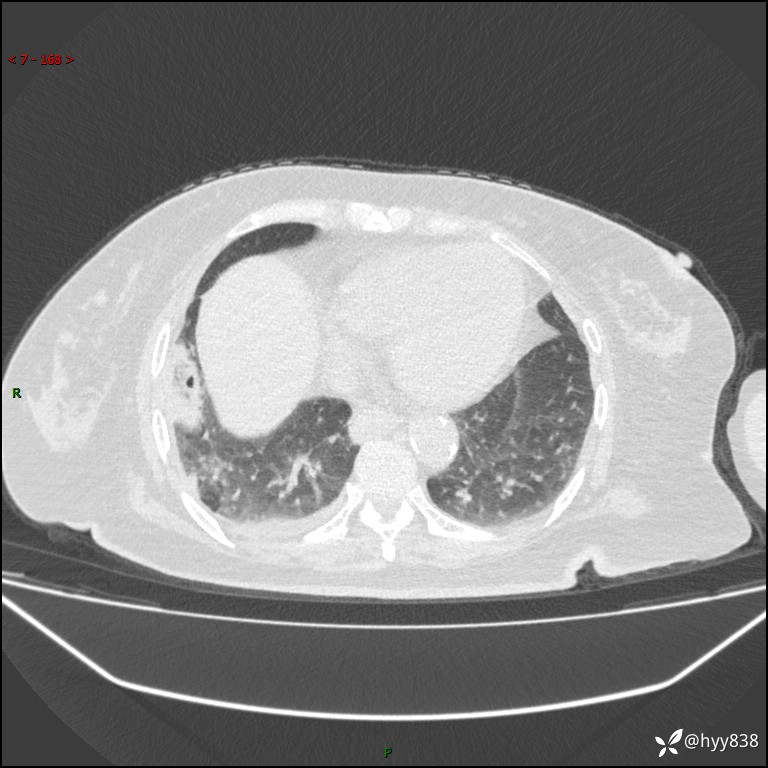

患者性别:女

患者年龄:57岁

简要病史:昏迷入院

胸部 CT平扫、